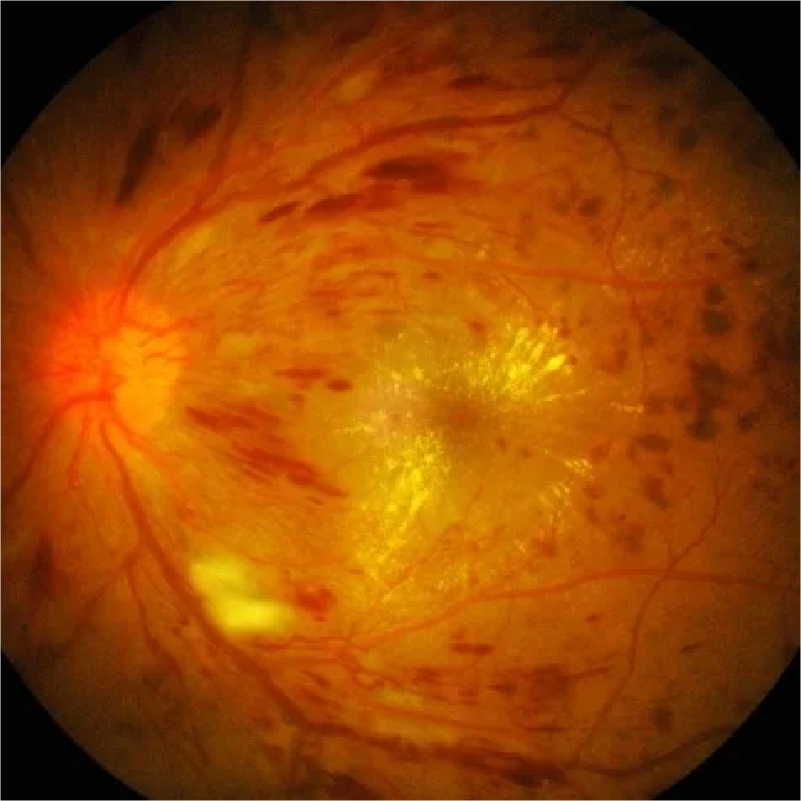

RETINOPATÍA DIABÉTICA

RETINOPATÍA DIABÉTICA

¿Que es la Retinopatía Diabética?

RETINOPATÍA DIABÉTICA

¿Qué es la retinopatía diabética?

La retinopatía diabética es una complicación de la diabetes que afecta a los vasos sanguíneos de la retina, la capa sensible a la luz en la parte posterior del ojo. Si no se trata, puede causar ceguera.

¿Por qué aparece la retinopatía diabética?

La diabetes puede dañar los vasos sanguíneos pequeños de la retina, lo que puede causar fugas de líquido y sangre. El número de años con diabetes y los niveles elevados de glucosa en la sangre son los principales factores de riesgo para desarrollarla.

Otros factores como hipertensión arterial descontrolada, niveles de colesterol y trigliceridos elevados, tabaquismo pueden acelerar la aparición de retinoaptía diabética.

¿Qué molestias produce la retinopatía diabética?

- Visión borrosa.

- Manchas oscuras o flotantes en la visión.

- Distorsión en la visión.

- Baja visión severa o ceguera.

¿Cómo se diagnostica la retinopatía diabética?

Con un examen de fondo de ojo, para el cual se le deberá de dilatar las pupilas para ver con detalle la totalidad de la retina.

Otros exámenes auxiliares como el OCT macular brinda detalles del área de mayor visión o mácula y la fluorangiografía con fluoresceina, que brinda detalles de la circulación retiniana.

¿Qué tipos de retinopatía diabética existen?

- Retinopatía diabética no proliferativa (NPDR): Es la etapa más temprana de la enfermedad. No hay crecimiento de nuevos vasos sanguíneos. Sin embargo, si no se trata puede evolucionar a severa.

- Retinopatía diabética proliferativa (PDR): Es la etapa más avanzada de la enfermedad. Se caracteriza por el crecimiento de nuevos vasos sanguíneos anormales en la retina. Estos vasos sanguíneos pueden ser frágiles y sangrar, lo que puede causar pérdida de la visión.

¿Cómo se trata la retinopatía diabética?

- Control de la diabetes: Mantener los niveles de azúcar en la sangre bajo control es la mejor manera de prevenir la retinopatía diabética y retrasar su progresión.

- Control de la presión arterial.

- Control del colesterol.

- Medicamentos antiangiogénicos: Inyecciones en el ojo que se usan para prevenir el crecimiento de nuevos vasos sanguíneos.

- Fotocoagulación con láser: Tratamiento con láser que se usa para disminuir las necesidades de oxígeno de la retina y mejorar la oxigenación de la misma.

- Vitrectomía: Cirugía para extirpar el gel vítreo del ojo, retirar membranas traccionales y aplicación de láser en la retina para el control de enfermedad.

¿Cuáles son las recomendaciones para un paciente con diabetes?

Es importante que las personas con diabetes se hagan exámenes oculares regulares para detectar y tratar la retinopatía diabética a tiempo. Se debe controlar la diabetes, la presión arterial, el colesterol y evitar el tabaquismo. Si tienes síntomas de retinopatía diabética, consulta conmigo para dar el tratamiento adecuado.